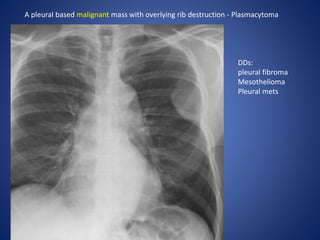

A pleural based malignant mass with overlying rib destruction - Plasmacytoma

DDs:

pleural fibroma

Mesothelioma

Pleural mets

A pleural basedmalignant mass with overlying rib destruction - Plasmacytoma DDs: pleural fibroma Mesothelioma Pleural mets